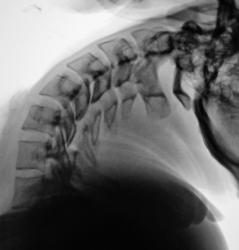

Рентгенограммы поясничного отдела позвоночника:

ИзображениеИзображениеИзображениеИзображение